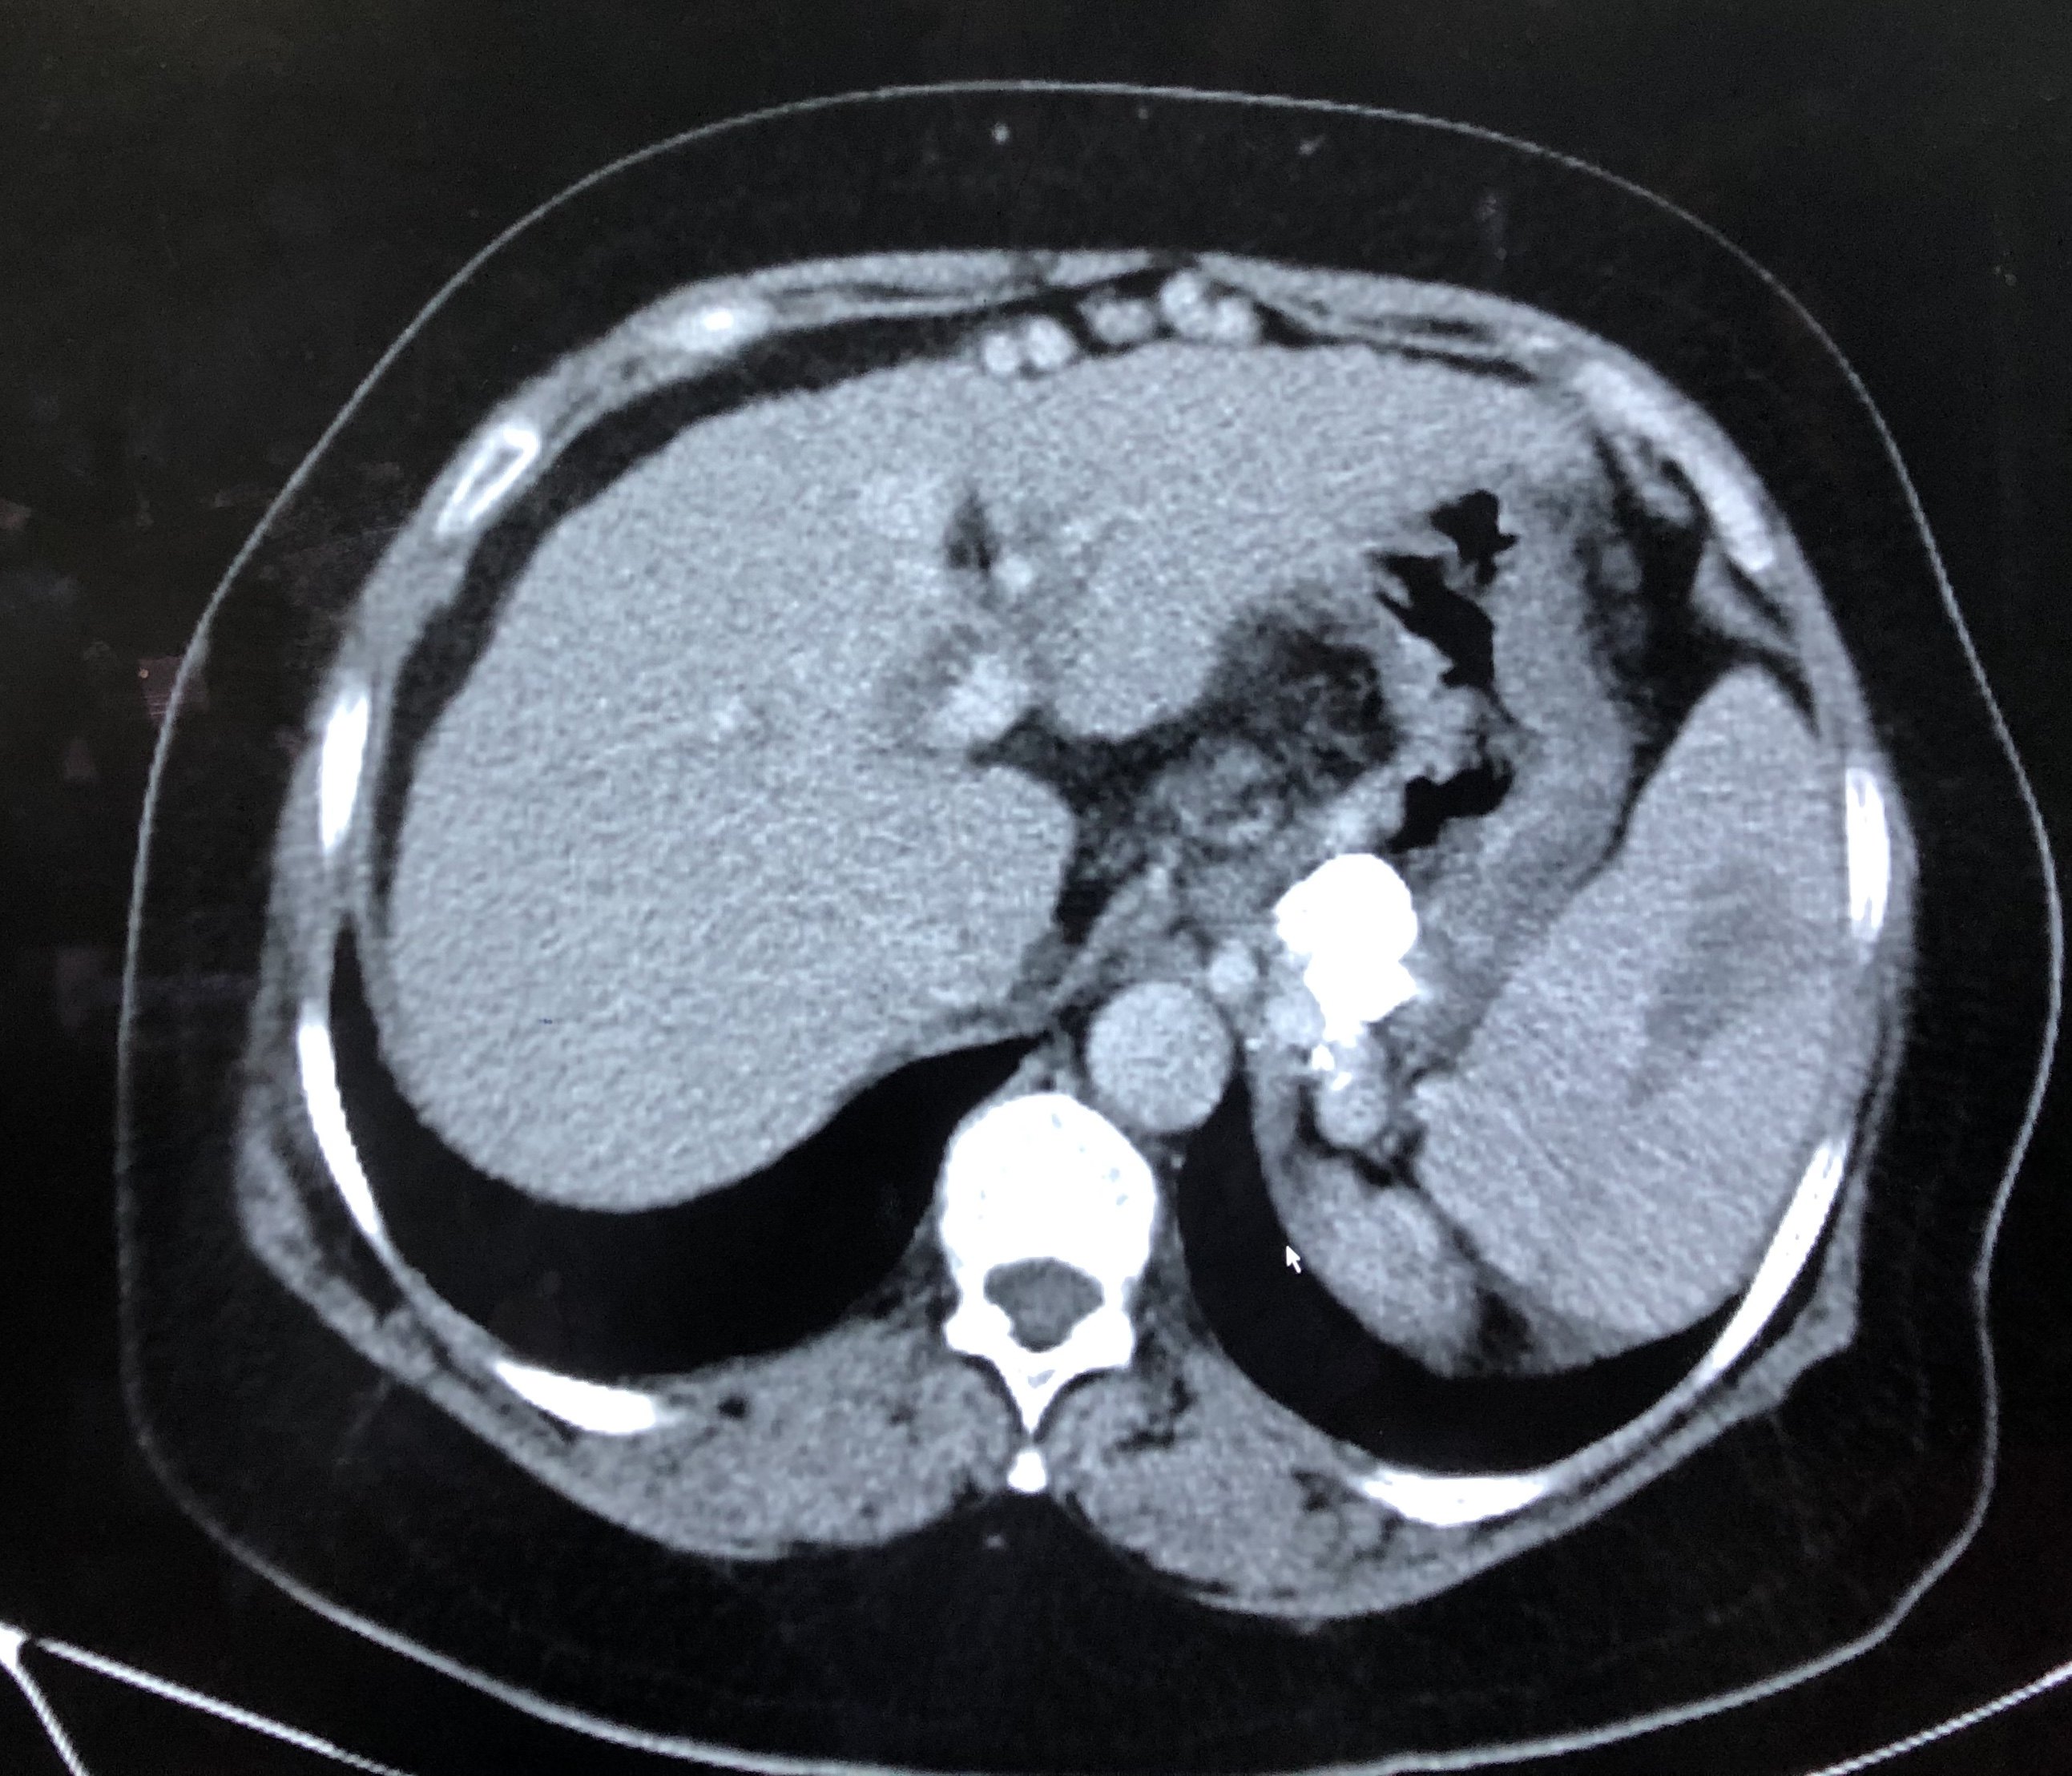

图1-1-2 脾脏肿大

图片尺寸827x992